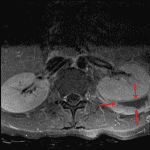

- Peripherally enhancing left posterior perinephric collection measuring 3.8 x 1.3 cm in maximum axial dimensions, incompletely imaged on this study, with surrounding enhancing soft tissue and anterior displacement of the left kidney

- 2.4 cm lesion in the medial interpolar left kidney which is hypoenhancing relative to the adjacent renal parenchyma

3.8 x 1.3 cm peripherally enhancing left posterior perinephric collection and 2.4 cm lesion in the medial interpolar left kidney are concerning for abscesses. Surrounding enhancing soft tissue and anterior displacement of the left kidney. Recommend further evaluation with contrast-enhanced CT of the abdomen and pelvis.